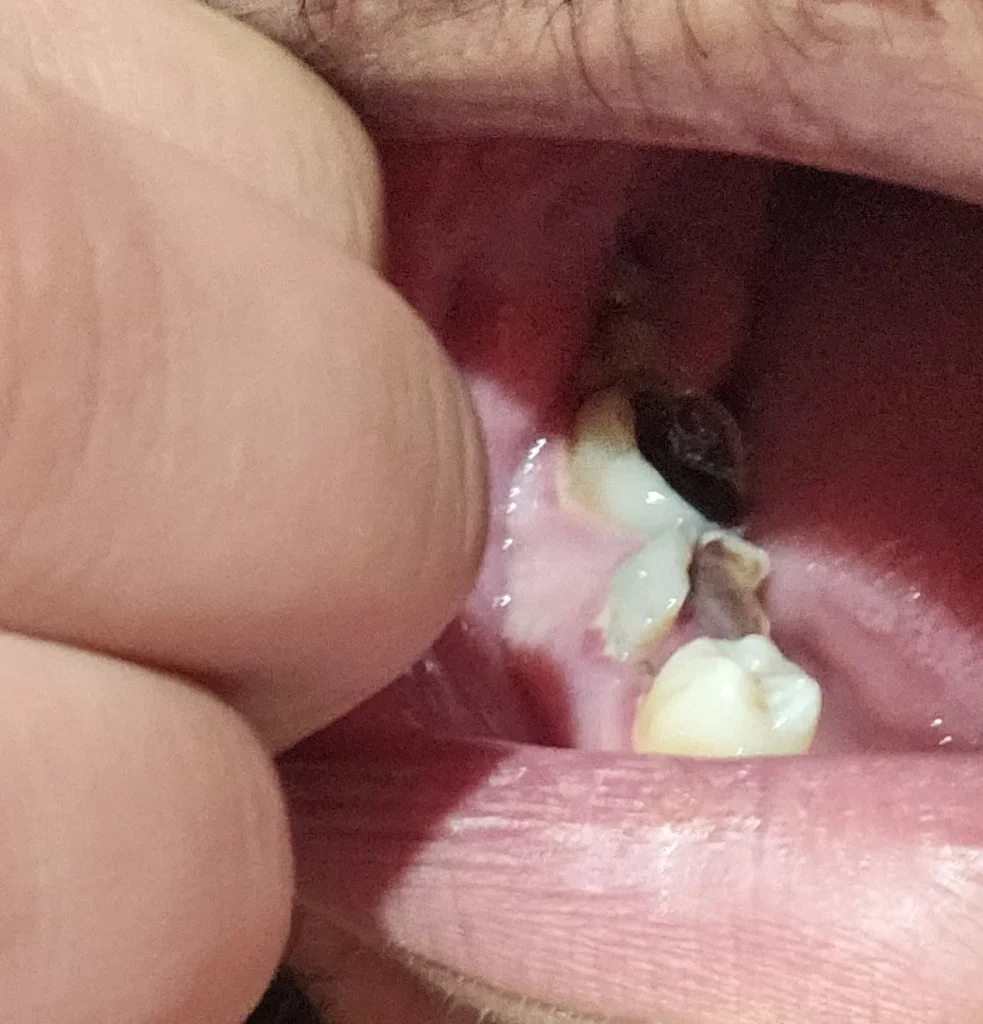

Se connecterإنتفاخ صلب بعض الشيء أسفل الضرس

Se connecterتسوّس عميق وصل إلى العصب وغالبا وجود التهاب قديم تحول الى انتفاخ قاس غالبا